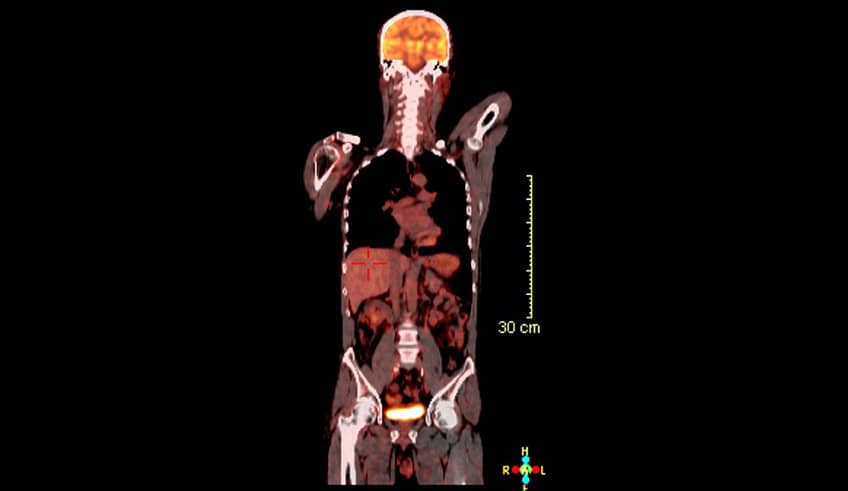

PET-CT scan showing FDG uptake patterns used in oncology imaging for 18F-FDG reporters training.

This course is designed to support Consultant Radiologists’ professional development to report PET-CT scans successfully. The Christie PET-CT Academy provides a learning platform designed to support consultant radiologists and radiology fellows trained in cross-sectional computed tomographic imaging to gain the necessary skills and experience to become an 18FDG PET-CT reporting radiologist.

Upon completion of this course, you will have a clear understanding of evidence-based use of PET-CT imaging in the clinical settings and be able to confidently read, interpret, report and review PET-CT scans. At the end of your training, you will have reported a total of approximately 400 to 600 cases (retrospective and 300 mentored prospective).